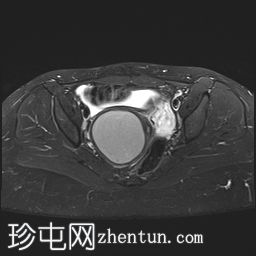

轴位

T1加权像

子宫腔重复畸形,表现为两个子宫体和两个宫颈。

右侧宫颈和子宫腔明显扩张,内部血流信号显示中央狭窄,T1加权像呈高信号,T2加权像呈低信号,脂肪抑制序列图像上无信号下降,内部可见持续低信号灶。最大轴位和冠状位直径分别为约6.5 x 6.4 x 14.2 cm。可见该肿块向前压迫膀胱,向后推移右侧卵巢,并紧贴左侧宫颈。

盆腔内可见少量游离液体,可能为生理性积液。